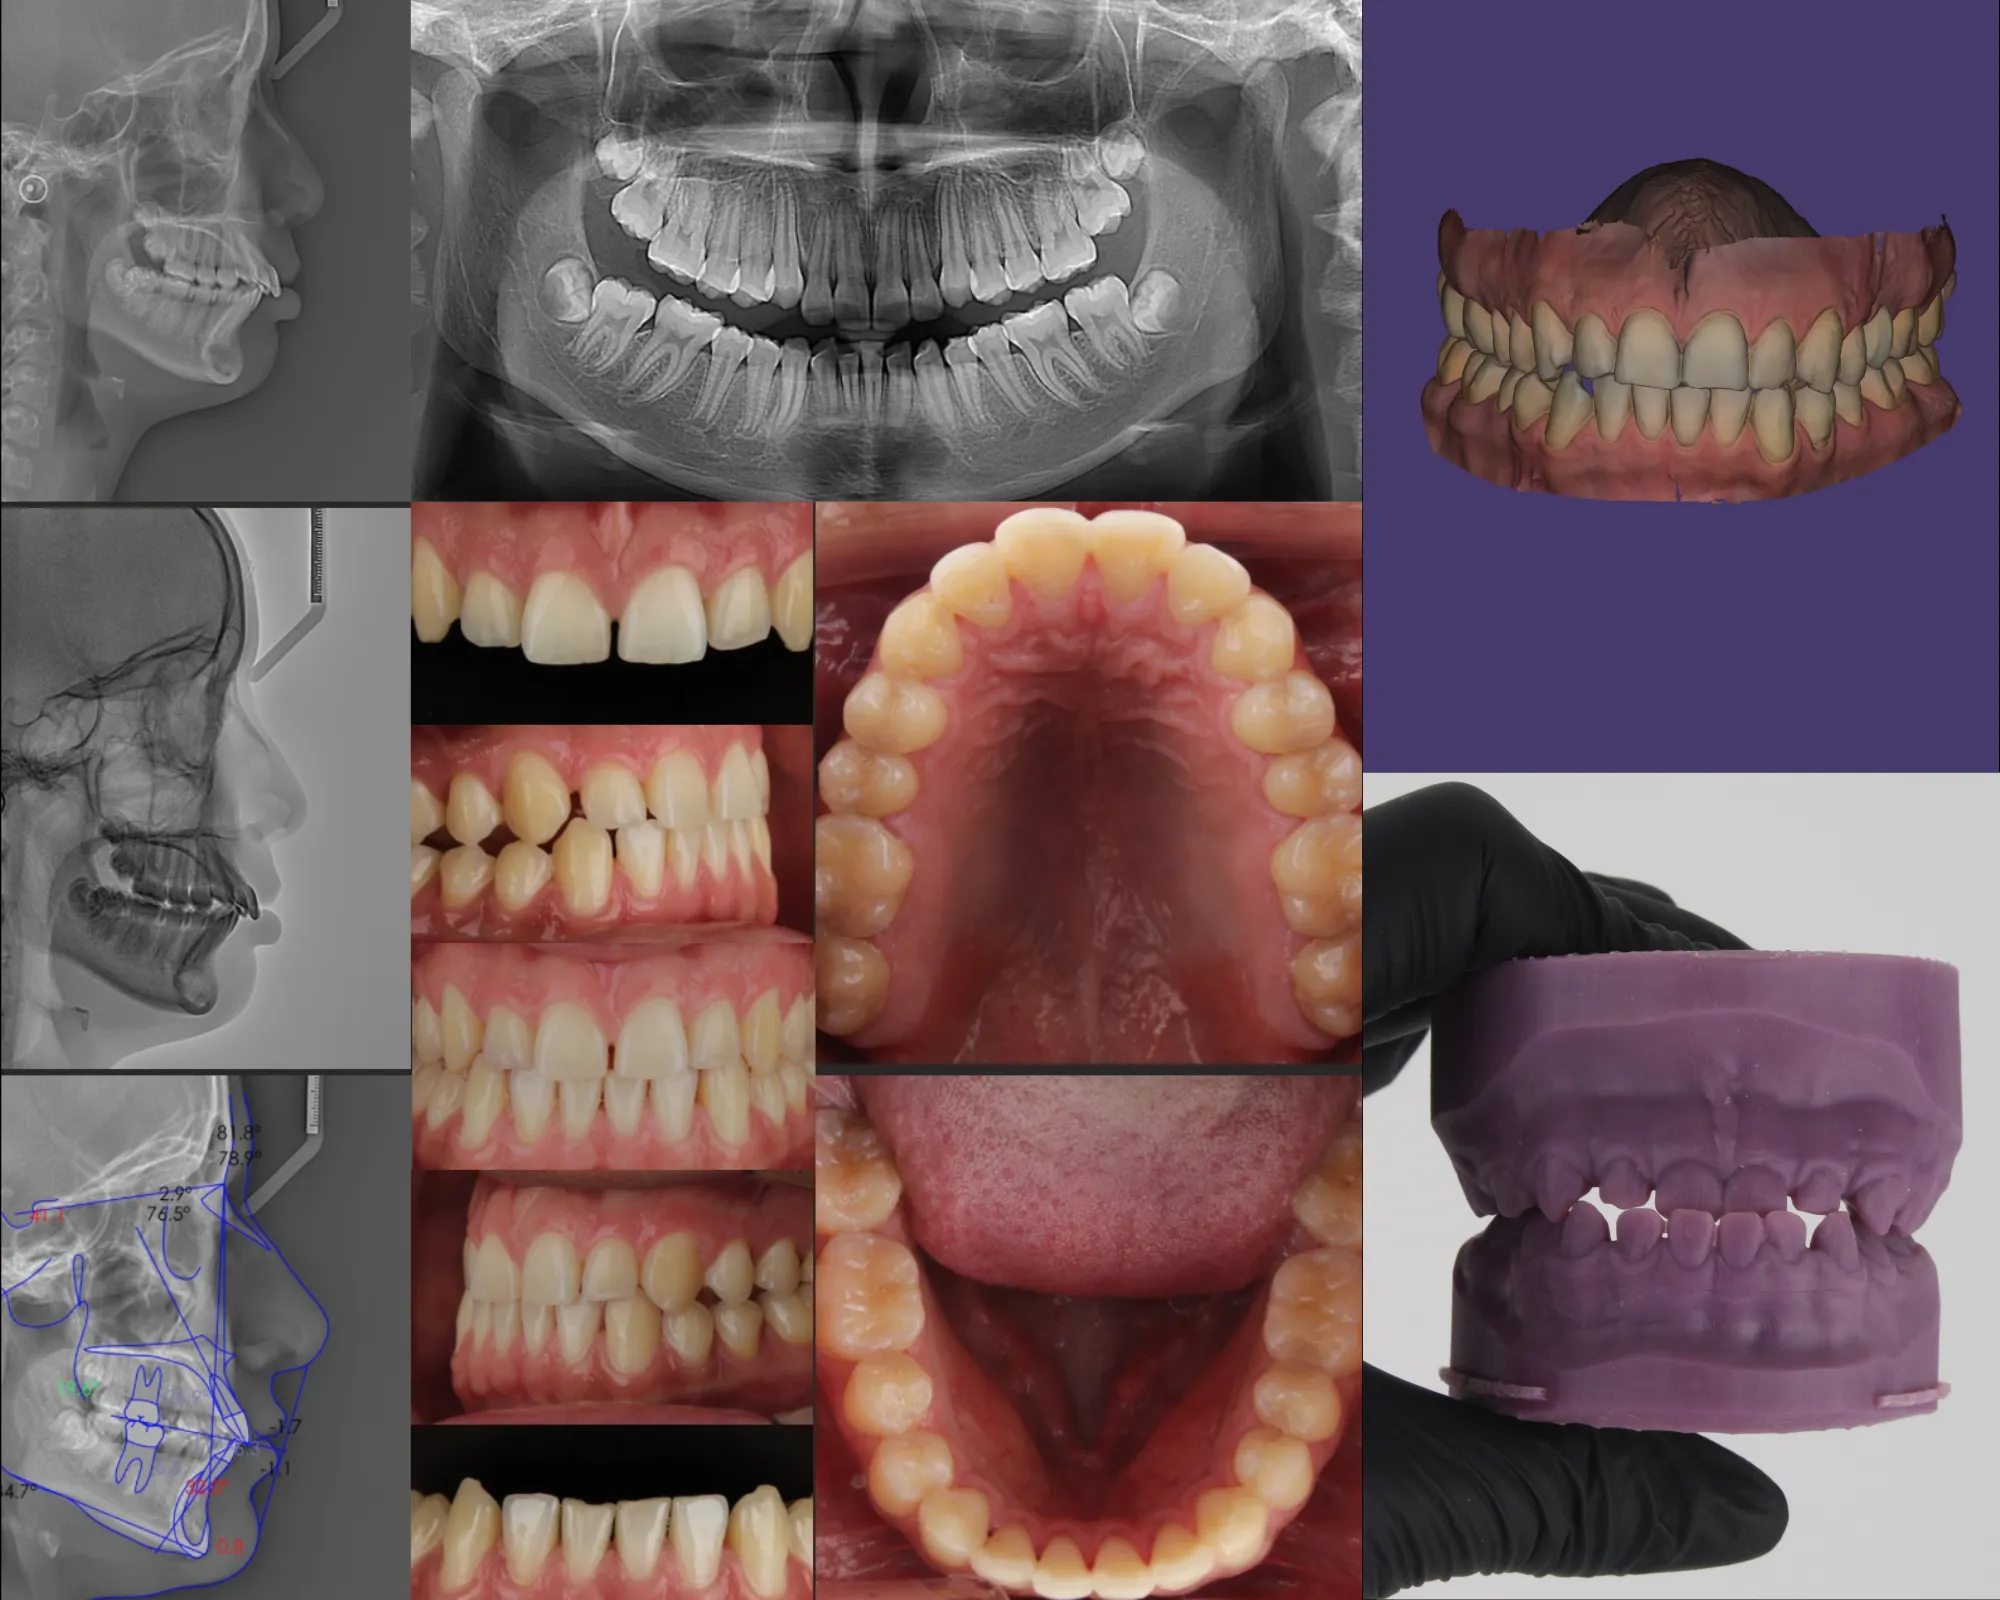

PAQUETE ORTODÓNTICO

Incluye: 02 Radiografías (panorámica y cefalométrica), fotografías extraorales, informe cefalométrico del análisis que se solicite (hasta 03 análisis).

PAQUETE ORTODÓNTICO 3D

Incluye: 02 radiografías (panorámica y cefalométrica), fotografías extraorales e intraorales (17 fotos), informe cefalométrico del análisis que se solicite (hasta 03 análisis), escaneo intraoral e impresión 3D.

ESCANEO INTRAORAL

Con nuestro escáner de la marca 3Shape captura impresiones directamente sobre la dentadura obteniendo una imagen en 3D, eliminando el sistema tradicional de impresiones físicas realizadas con alginato.

IMPRESIONES 3D

Modelos dentales en un tiempo más corto y con mayor precisión, lo que beneficia tanto a los pacientes como a los profesionales.